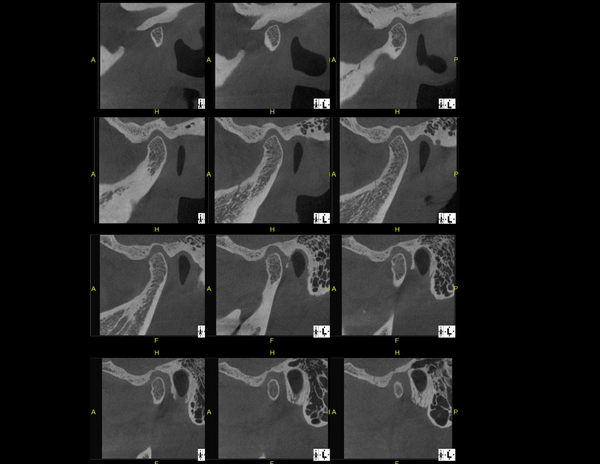

A Tomografia Computadorizada pela técnica do feixe cônico/cone beam (CBCT) introduziu um novo conceito de tomografia computadorizada na região bucomaxilofacial, que por meio da rápida aquisição volumétrica produz imagens com altíssimo grau de definição e fidelidade, além da redução na dose total de radiação emitida ao paciente.

Além disso, ocorre a minimização dos artefatos de imagem em relação à TC médica, o que torna possível a realização de imagens com qualidade diagnóstica e precisão sub-milimétrica, mesmo na presença de estruturas metálicas (restaurações, pinos/núcleos, aparelhos ortodônticos).